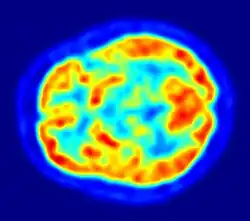

PET imaging with FDG takes advantage of the fact that the brain is normally a rapid user of glucose. Standard FDG PET of the brain measures regional glucose use and can be used in neuropathological diagnosis.

Brain pathologies such as Alzheimer's disease greatly decrease brain metabolism of both glucose and oxygen in tandem. Therefore FDG PET of the brain may also be used to successfully differentiate Alzheimer's disease from other dementing processes, and also to make early diagnoses of Alzheimer's disease. The advantage of FDG PET for these uses is its much wider availability. In addition, some other fluorine-18 based radioactive tracers can be used to detect amyloid-beta plaques, a potential biomarker for Alzheimer's in the brain. These include florbetapir, flutemetamol, Pittsburgh compound B (PiB) and florbetaben.[18]